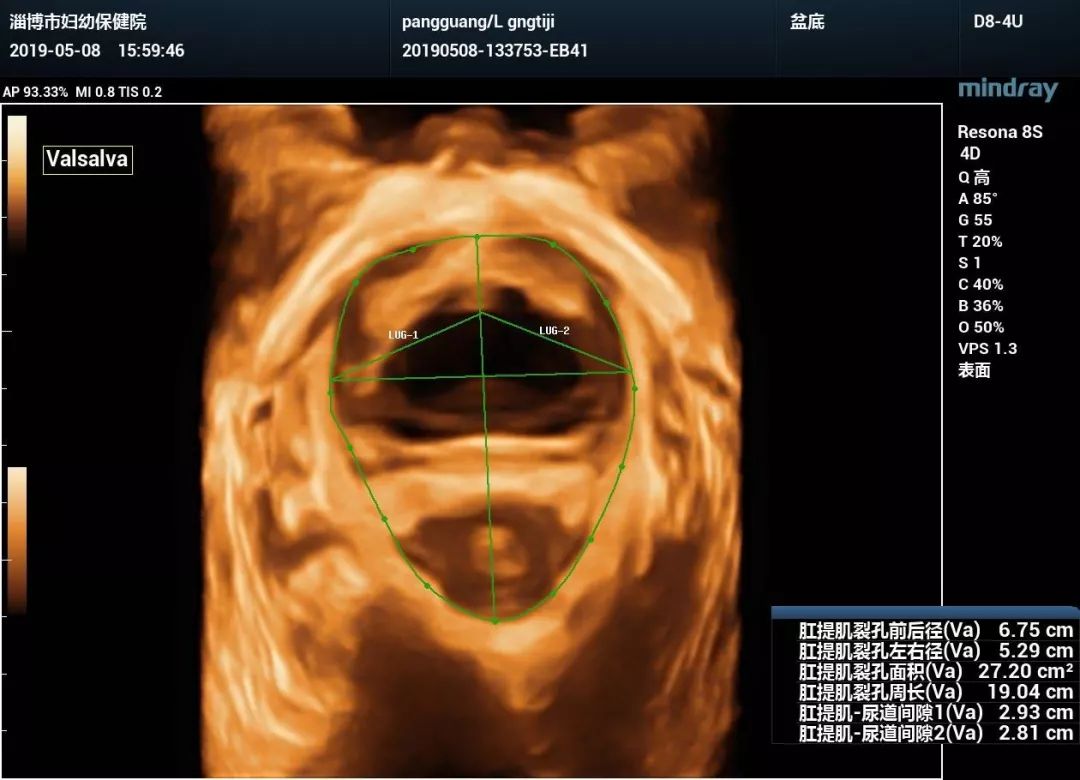

(盆底正中矢状切面valsalva状态)(盆底正中矢状切面静息状态)关爱女性